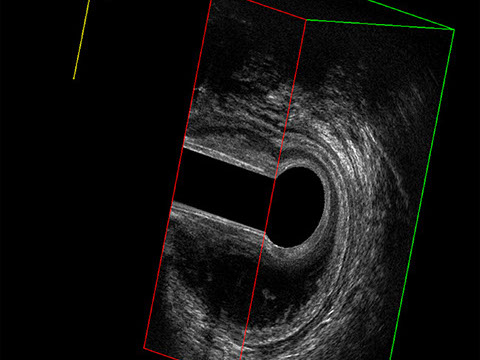

L’ecografia transanale è un esame diagnostico per immagini che consiste nell’introduzione di un trasduttore ad ultrasuoni. Le immagini qualitativamente migliori del canale anale sono ottenute usando un trasduttore rotante, montato in un manipolo rigido, che fornisce un’immagine a 360°. Con le apparecchiature più moderne è anche possibile ottenere immagini tridimensionali.

Proctal dispone di apparecchiatura per ecografia endoanale 3D con sonda rotante.